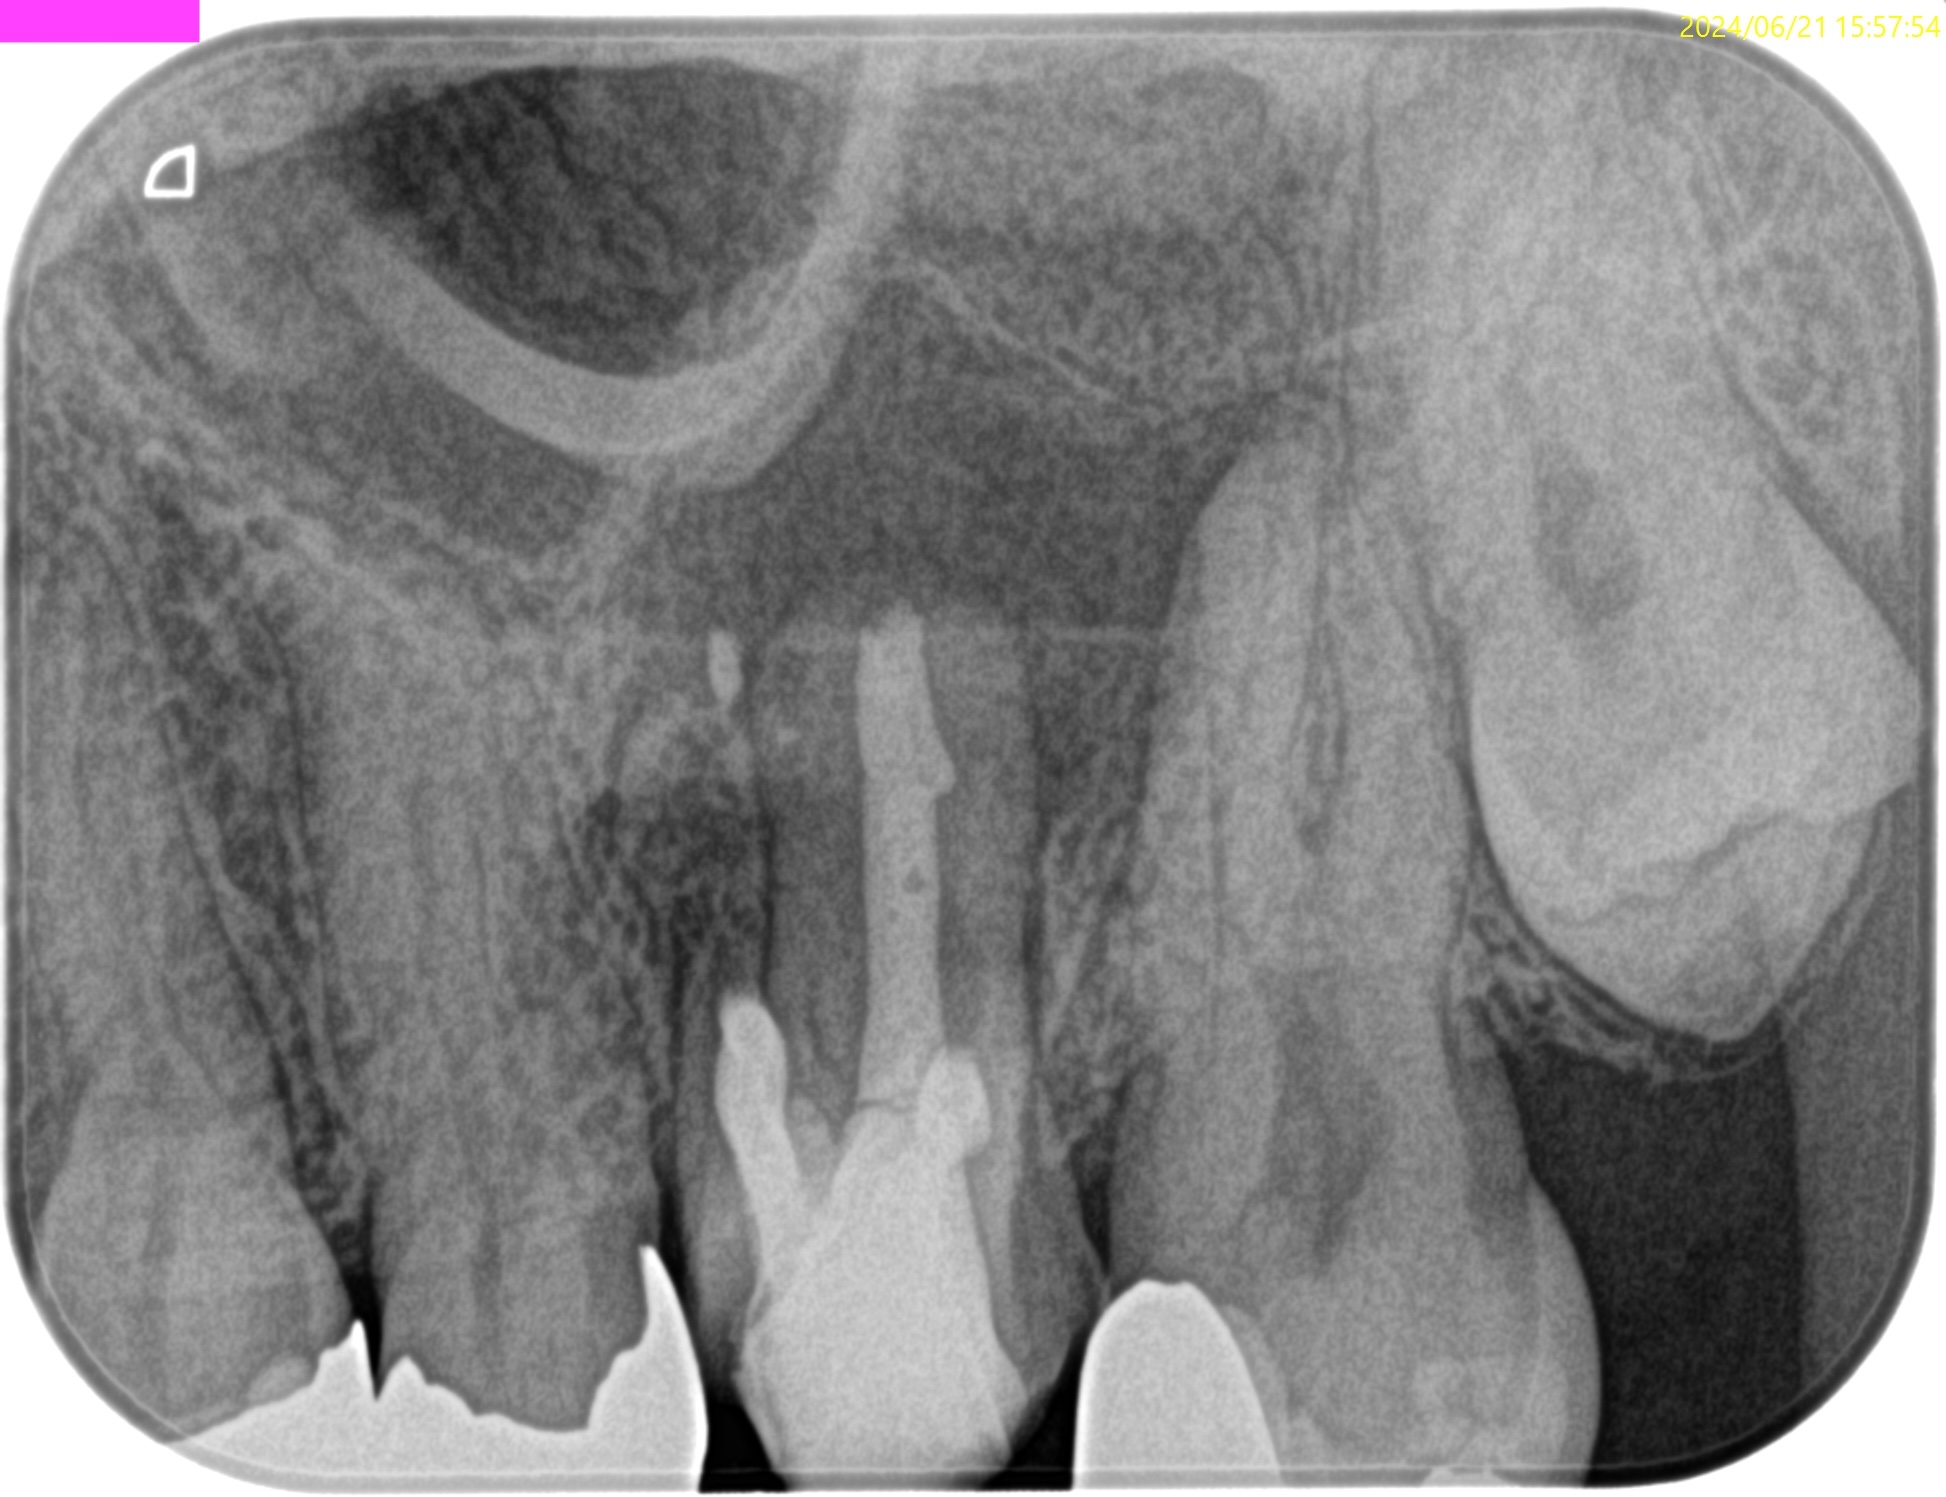

#14 Re-RCT 1yr recall(2024.6.10)

MB

DB

P

1年前よりも状況がひどくなる。

そこで、Apicoectomyを行うのだが、

MB,DB,Pの3根同時の根切が必要であったので、

Flapを開けてMB,DBを短く切断してその上でIntentional Replantationを行うと言う治療計画にした。

すると1回法で終了するからだ。